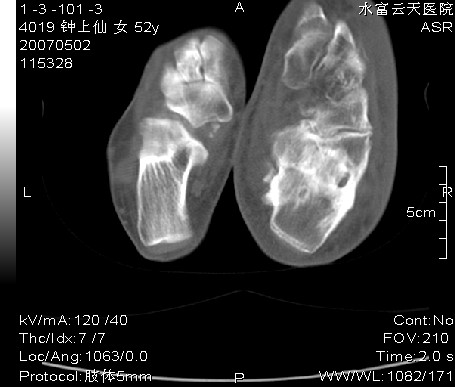

右足跗骨关节面毛糙,滑膜下多发虫蚀状破坏区,周围有硬化边,软组织肿胀明显,首先考虑关节结核;结合实验室检查及平片排除创伤性关节炎合并化脓性感染。

右足跗骨关节面毛糙,滑膜下多发虫蚀状破坏区,并形成空洞及见空洞内死骨,周围有硬化边,软组织肿胀明显,支持首先考虑:右足跗骨结核。

右跟骨轻度膨胀,轮廓不规则,见明显增生硬化,且见斑片状骨破坏及小死骨形成,有软组织肿胀明显,皮下脂肪密度增高。考虑右跟骨陈旧性骨折,右跟骨化脓性骨髓炎

右足跗骨关节面毛糙,滑膜下多发虫蚀状破坏区,并形成空洞及见空洞内死骨,周围有硬化边,软组织肿胀明显,支持首先考虑:1:右糖尿病足,查血糖.2右足骨髓炎

右足跗骨关节面毛糙,滑膜下多发虫蚀状破坏区,周围有硬化边,软组织肿胀明显,首先考虑创伤性关节炎合并化脓性感染;结关节结核合实验室检查及平片排除。